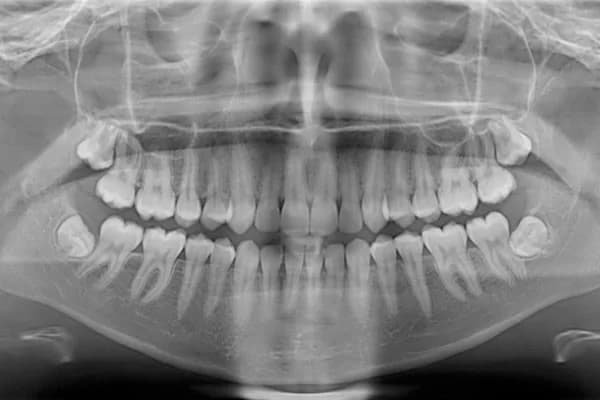

- Radiografías / CBCT / RM según el caso.